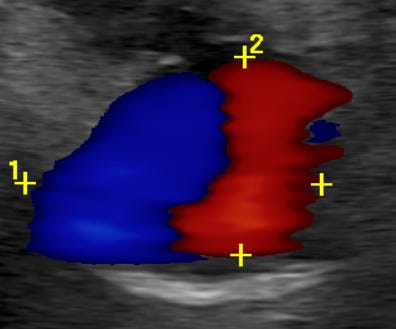

Color Doppler demonstrates the pathognomonic “Yin-Yang” sign—a swirling pattern of blood flow within the sac. This distinctive appearance results from blood flowing into the pseudoaneurysm during systole and back out during diastole.

The tech got a great shot of the Yin-Yang sign, below: